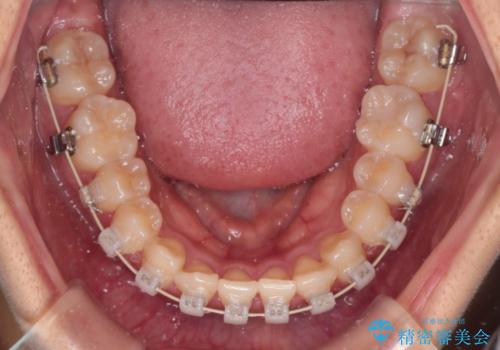

抜かない矯正 審美装置によるワイヤー治療

- 矯正装置

- 審美装置

- 前歯のガタガタを主訴に来院されました。

インビザラインも提案しましたが、装着時間を確実に確保できるか不安ということもありワイヤー矯正を希望されました。

装着時間に不安がある人は、ワイヤー矯正をおすすめしております。短期間で治療でき患者様にも満足していただきました。